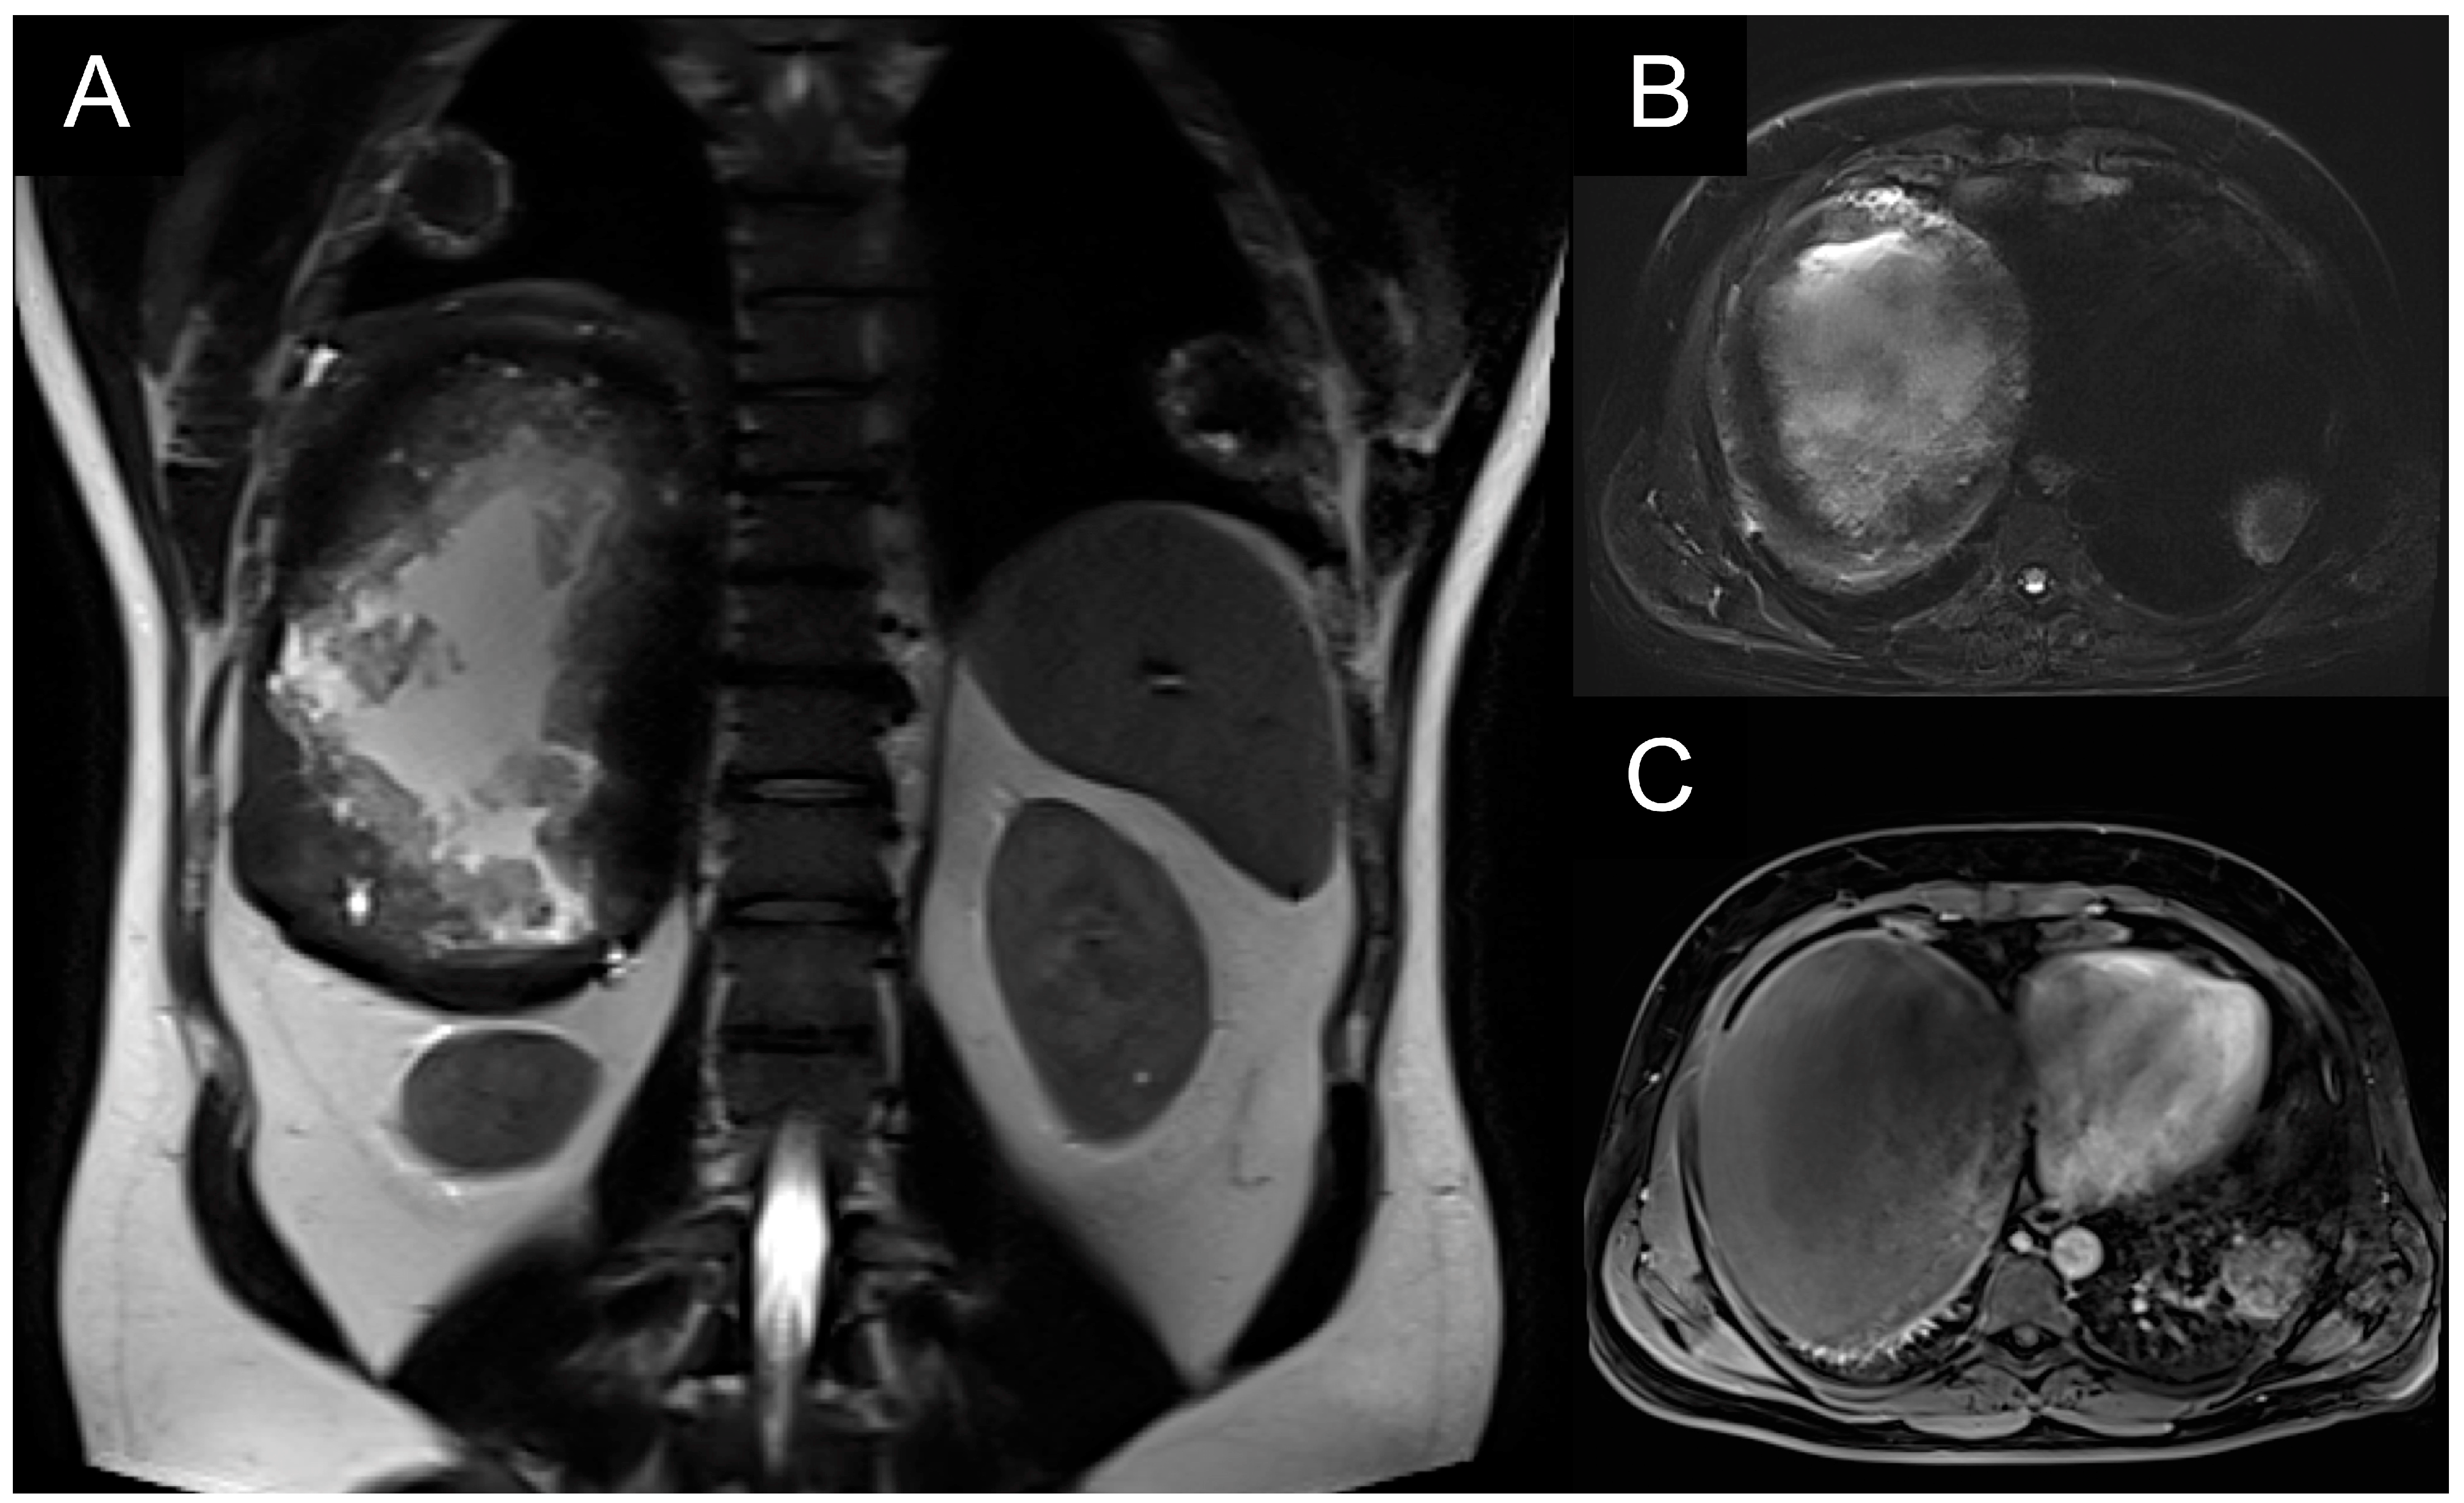

A patient with multiple bilateral lung lesions was diagnosed after investigations for a large hepatic lesion that turned out to be echinococcosis. A 41-year-old male patient reported abdominal pain and shortness of breath and was referred to the hospital by a primary care physician. Primary radiological investigations revealed a large hepatic lesion and multiple bilateral pulmonary lesions. Magnetic resonance imaging (MRI) was performed to evaluate the hepatic lesion (Figure 1), while chest X-rays and computed tomography (CT) were performed prior to admission to the Department of Thoracic Surgery. CT detected two right lower lobe lesions in segment 6 (diameters 4.6 cm, 1.4 cm) and one in segment 8 measuring 1 cm. In the left lower lobe, there was a single 4 cm lesion in segment 9 (Figure 2).

Figure 1. (A,B): T2-weighted hyperintense liver lesion; (C): T1-weighted hypointense liver lesion with abnormal pulmonary lesions.